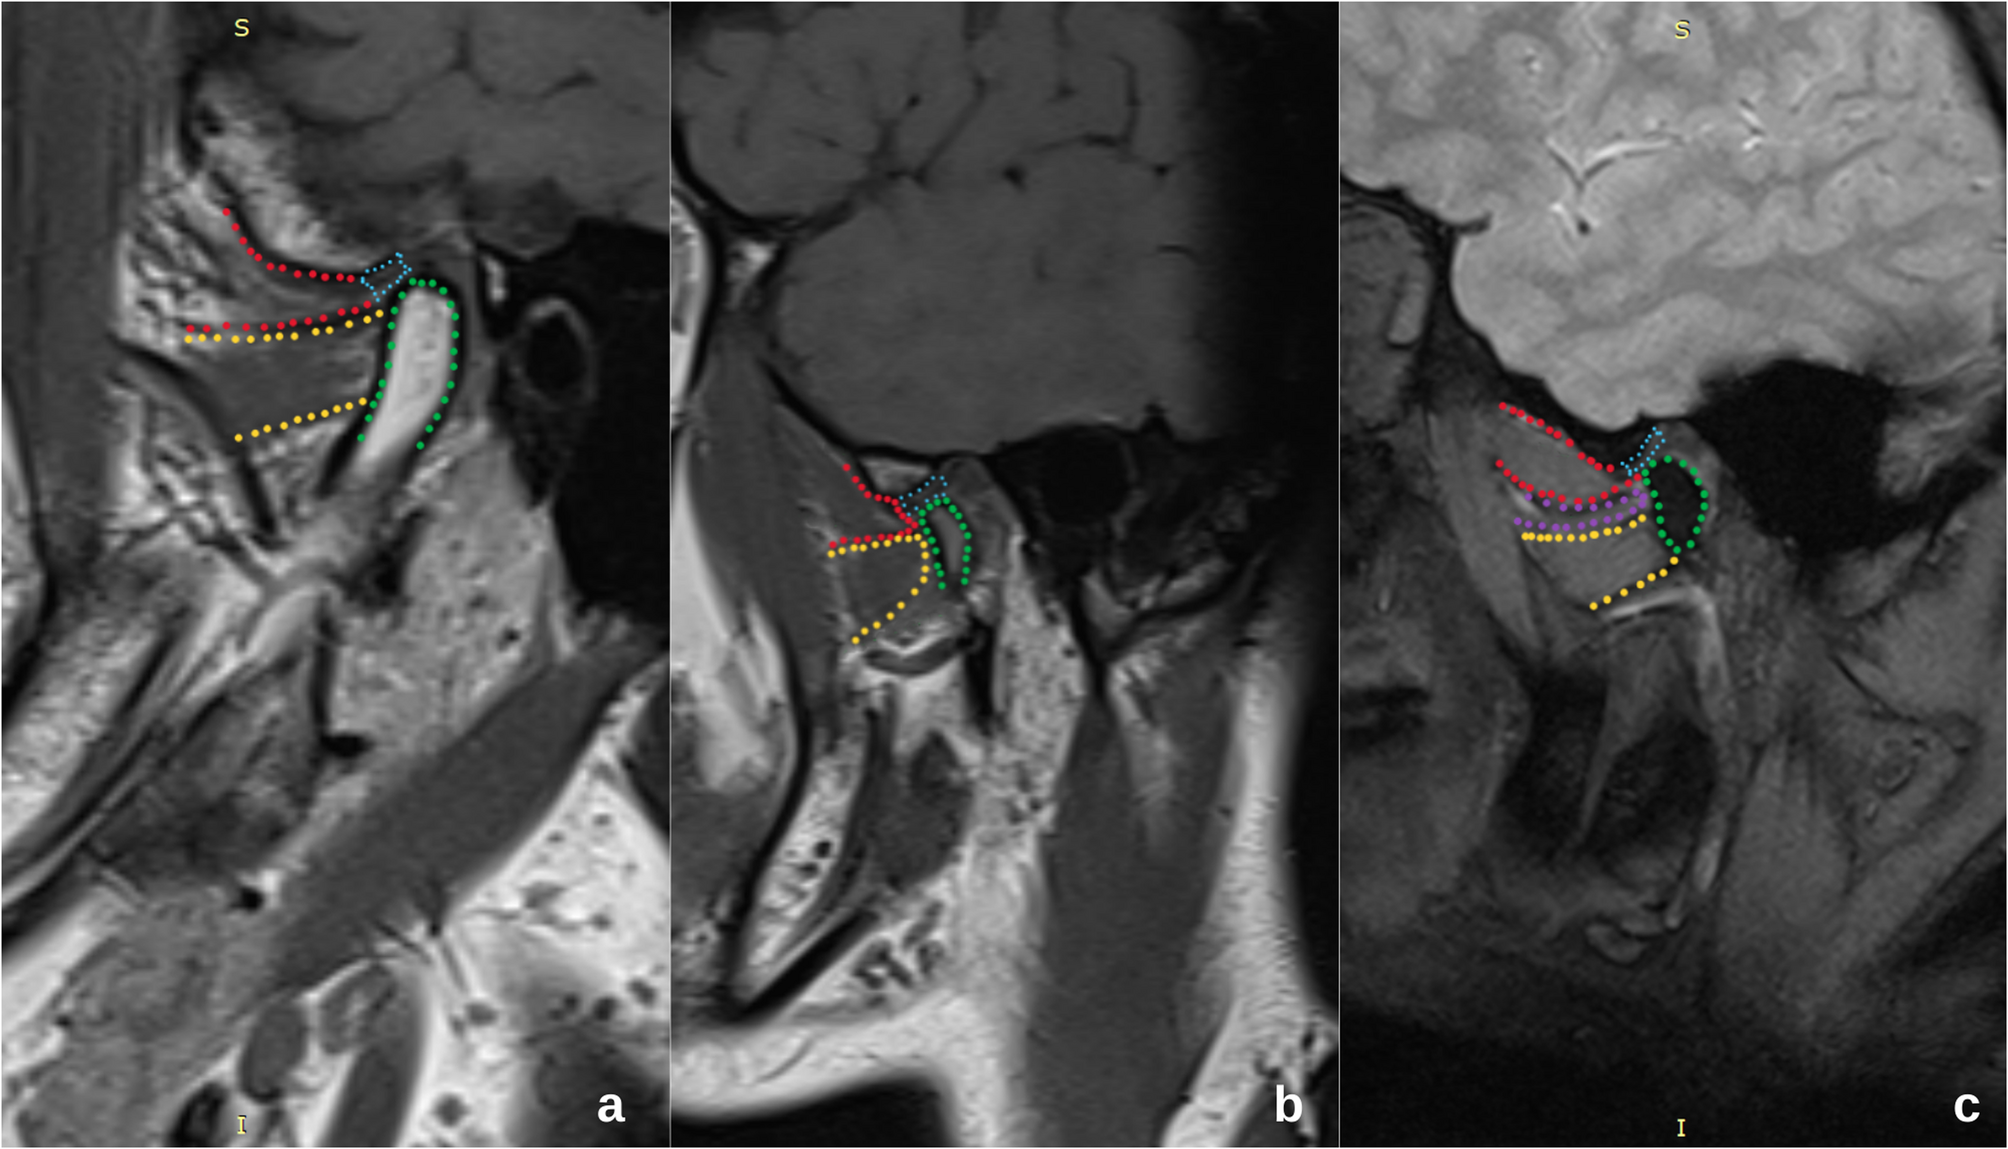

Evaluation of the correlation between articular disc displacement and the lateral pterygoid muscle using magnetic resonance imaging | BMC Oral Health